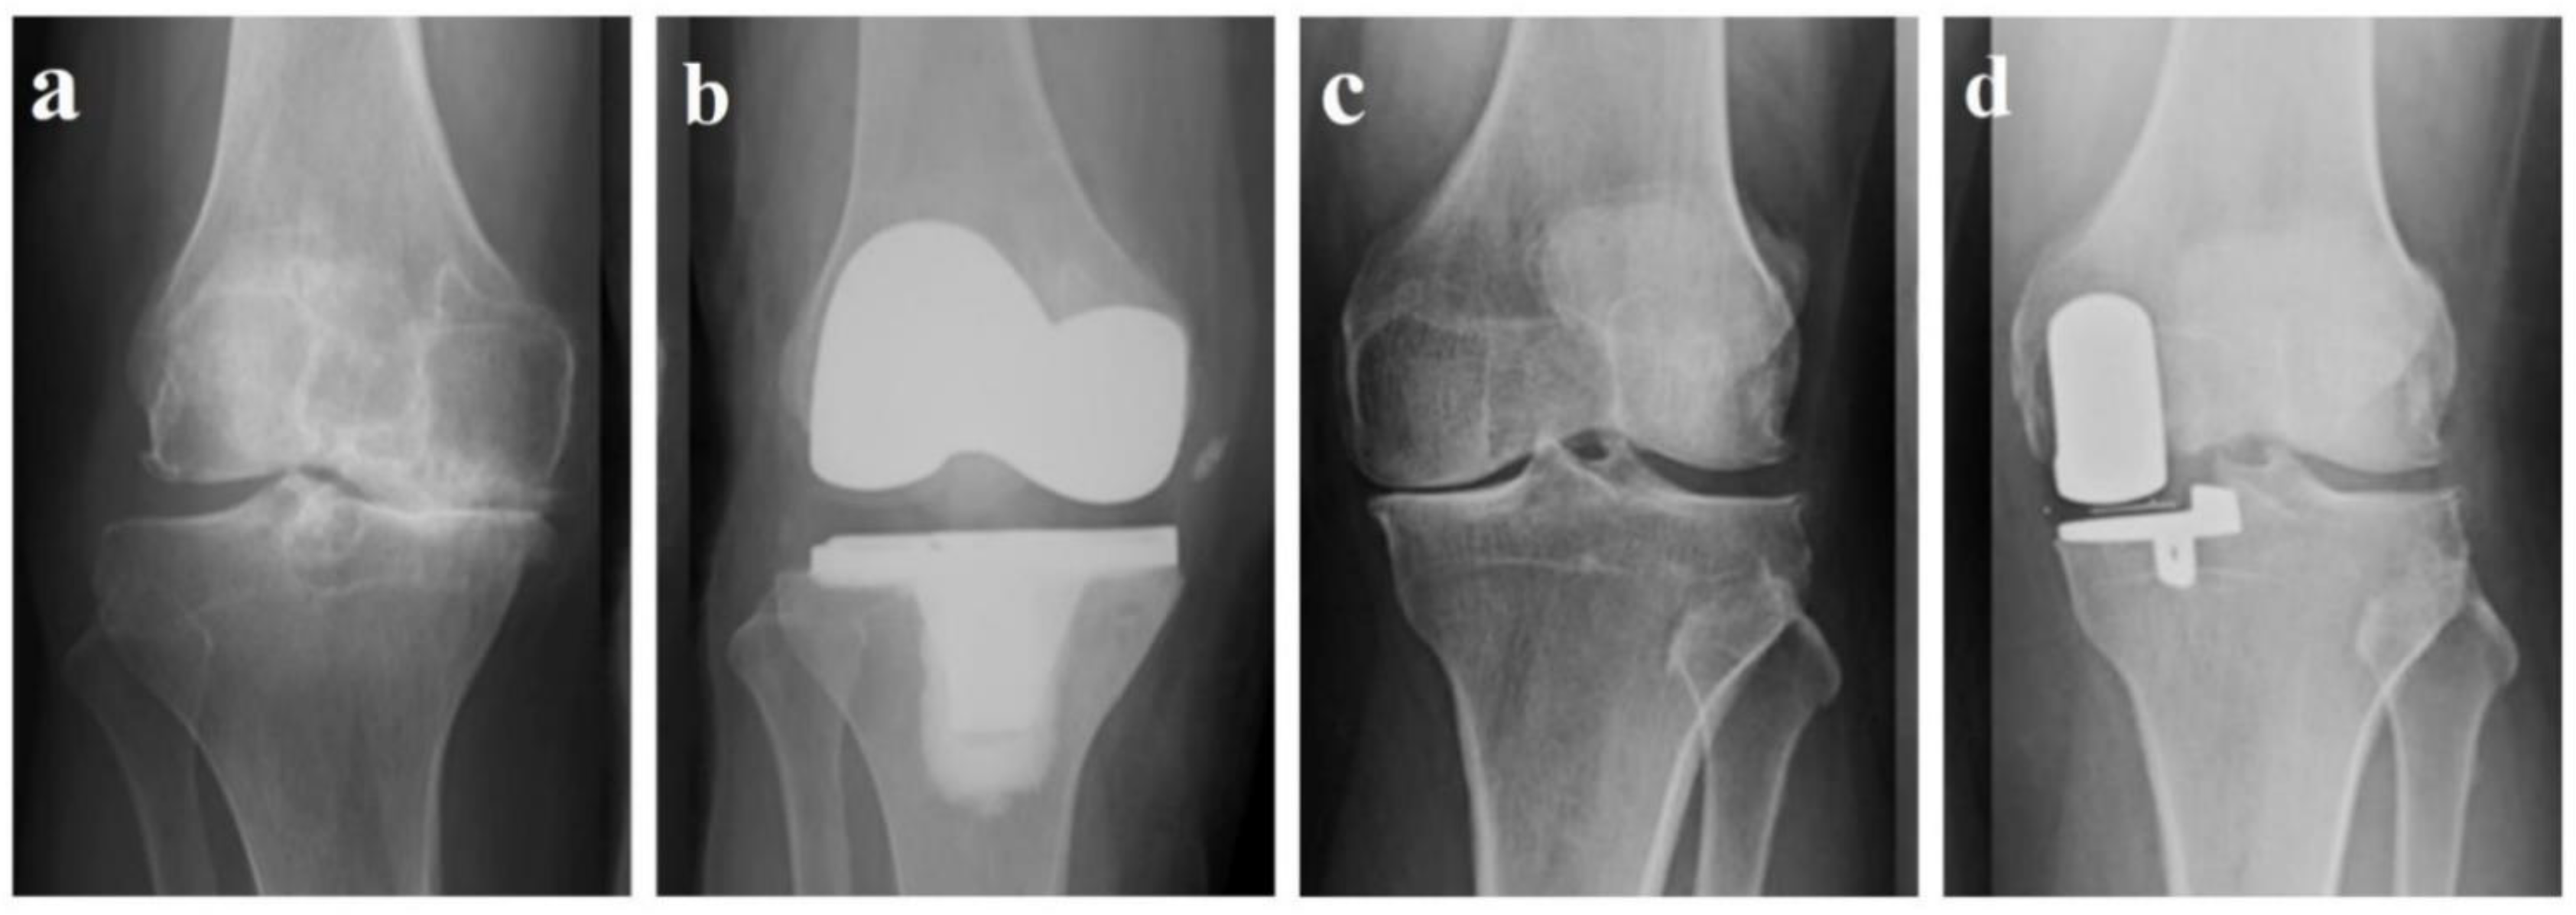

NexGen RH Knee (Zimmer Biomet, Warsaw, IN) in (a)anteroposterior, (b Zimmer Biomet Total Knee Technique A leading implant among surgeons in the united states, our persona knee implant has a. Zimmer biomet tv provides a comprehensive video. Rosa® knee 1.4 surgical technique. Persona® the personalized knee® surgical technique. Zimmer biomet tv provides a. Zimmer biomet’s vanguard ® knee system features two knee implant options so that surgeons may select an implant specifically. Zimmer Biomet Total Knee Technique.